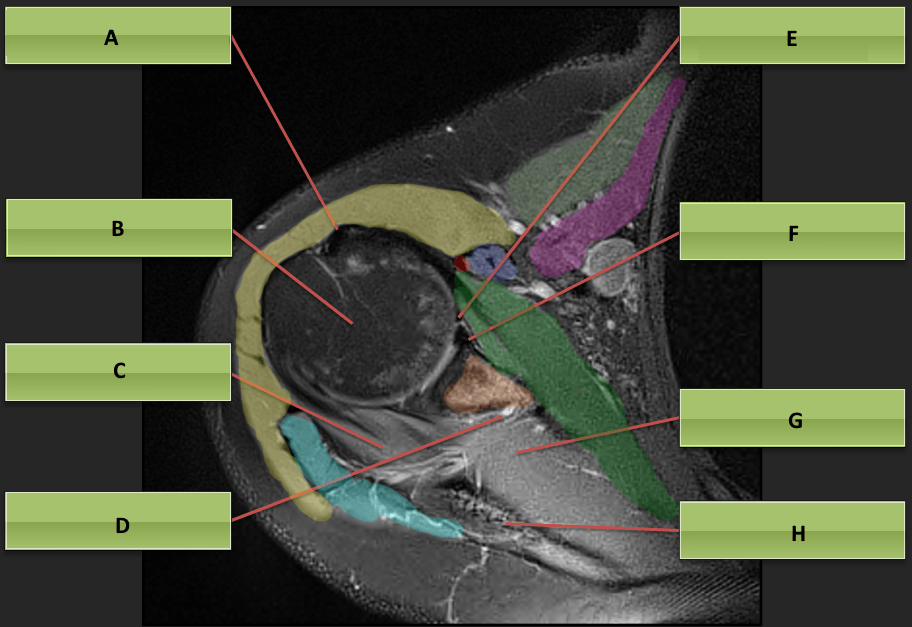

Axial MRI Shoulder Anatomy

Axial MRI Shoulder Anatomy Mri Anatomy Axial The anatomy of the brain is studied by means of axial, coronal and sagittal views. Mri scans, much like computed tomography, typically produce three anatomical views; A review of brain magnetic resonance imaging (mri) is used as support. Note, however, that mcrae’s line (basion. When interpreting axial views, it is. It enables clinicians to focus on various parts of the. Mri Anatomy Axial.

shoulder anatomy mri shoulder axial anatomy free cross sectional Mri Anatomy Axial It is the most complete reference of human anatomy available. Note, however, that mcrae’s line (basion. The mri sequence used is a 3d gradient. The anatomy of the brain is studied by means of axial, coronal and sagittal views. When interpreting axial views, it is. Mri axial cross sectional anatomy of brain. A brain mri is one of the most. Mri Anatomy Axial.

Axial MRI Shoulder Anatomy Mri Anatomy Axial Sagittal, coronal and axial (similar to the planes of the body). The mri sequence used is a 3d gradient. When interpreting axial views, it is. A brain mri is one of the most commonly performed techniques of medical imaging. Mri scans, much like computed tomography, typically produce three anatomical views; It is the most complete reference of human anatomy available.. Mri Anatomy Axial.